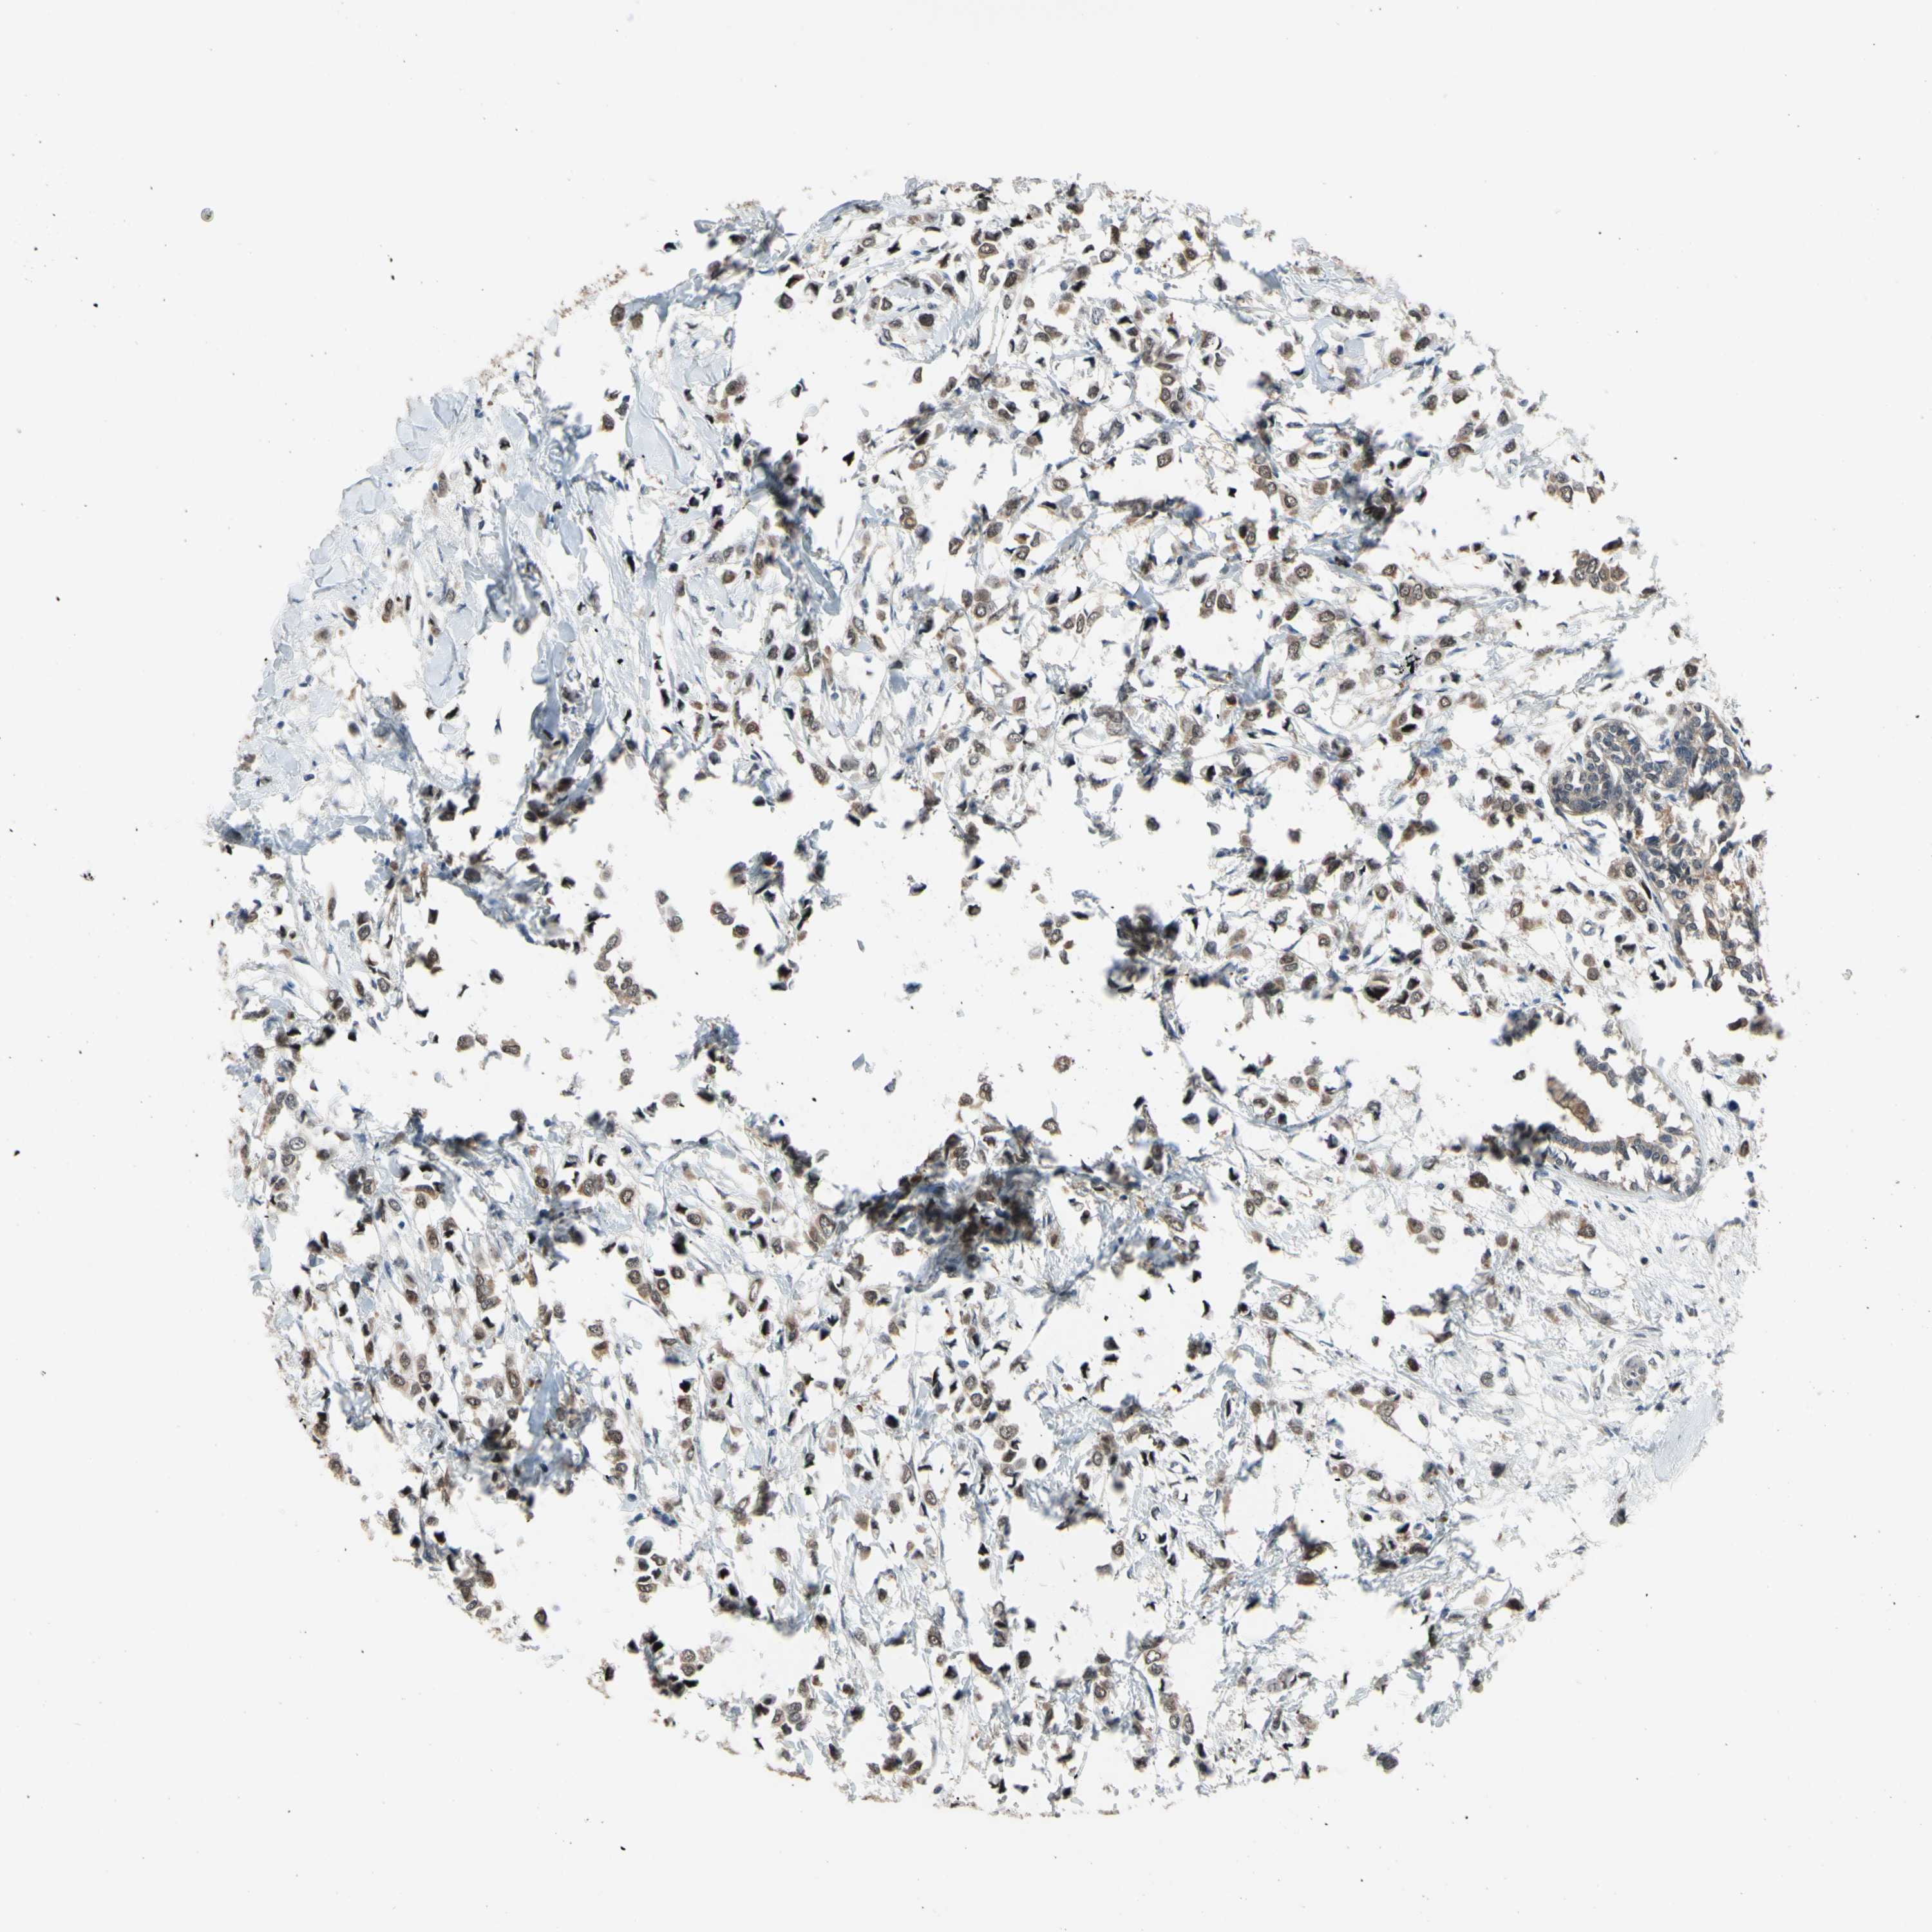

CANCER BREAST CANCER Show tissue menu

BRCA TCGA BRCA VALIDATION PROTEIN EXPRESSION